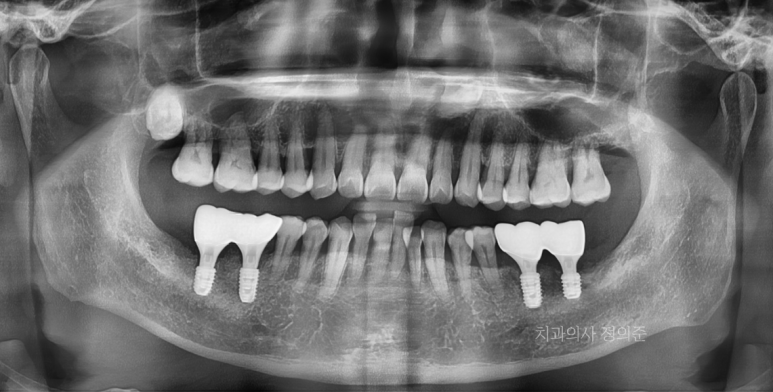

2023. 7 치료 전

2024. 6 정기검진 시

왼쪽 아래 첫번째 큰 어금니의 경우 큰 무리없이 임플란트 수술이 가능하여 1주일 정도 더 기다린 후에

임플란트 수술을 진행하였습니다. (우측 파노라마 사진)

다만, 빠진 2개의 치아 중 제일 뒤쪽 (왼쪽 아래 두번째 큰 어금니)의 잇몸뼈가 많이 부족한 상태셨고,

아래턱 신경과 매우 근접하였기 때문에 안전한 임플란트 식립을 위하여 3개월 정도 회복을 기다린 후에

수술 전에 "서지컬 가이드"라는 장치를 만들고 수술하는 것으로 계획하였습니다.

수술이 잘 마무리 되었고, 먼저 수술한 임플란트는 임시보철물로 식사가 가능하도록 하였습니다.

2023. 10

약 2개월의 회복 기간을 갖고, 2차 수술 및 보철과정을 진행하였습니다.

과정은 구강스캐너인 "3Shape Trios 4"를 이용하여 진행되었고,

아래와 같이 치료는 잘 마무리 되었습니다.